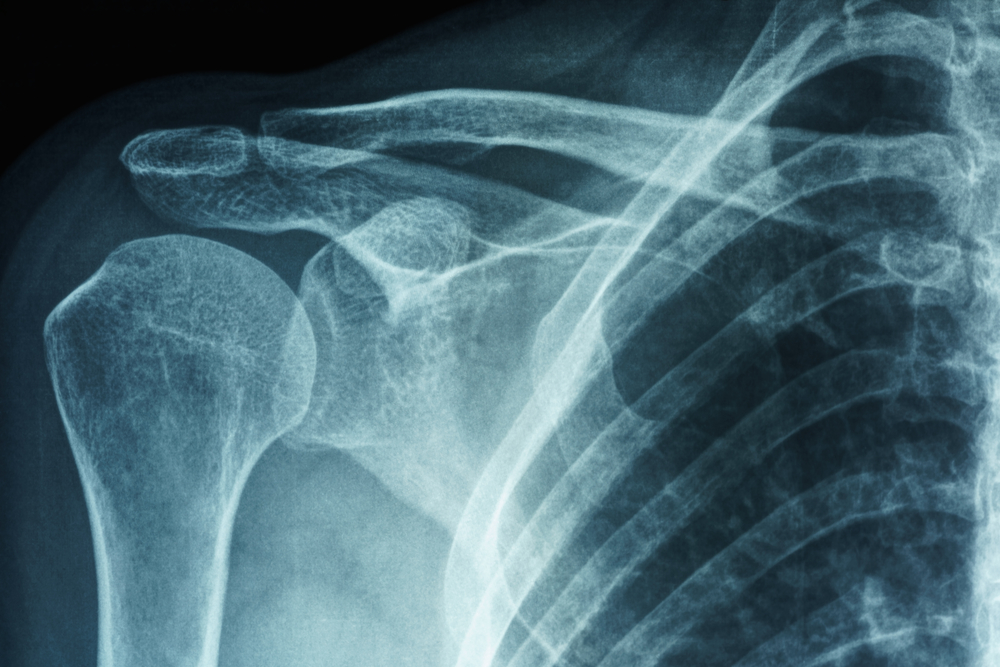

Dor no ombro: conheça as principais causas e sintomas

Desgaste natural da articulação e inflamações nas estruturas que compõem o ombro são as principais causas de dor na regiãoO ombro é uma...